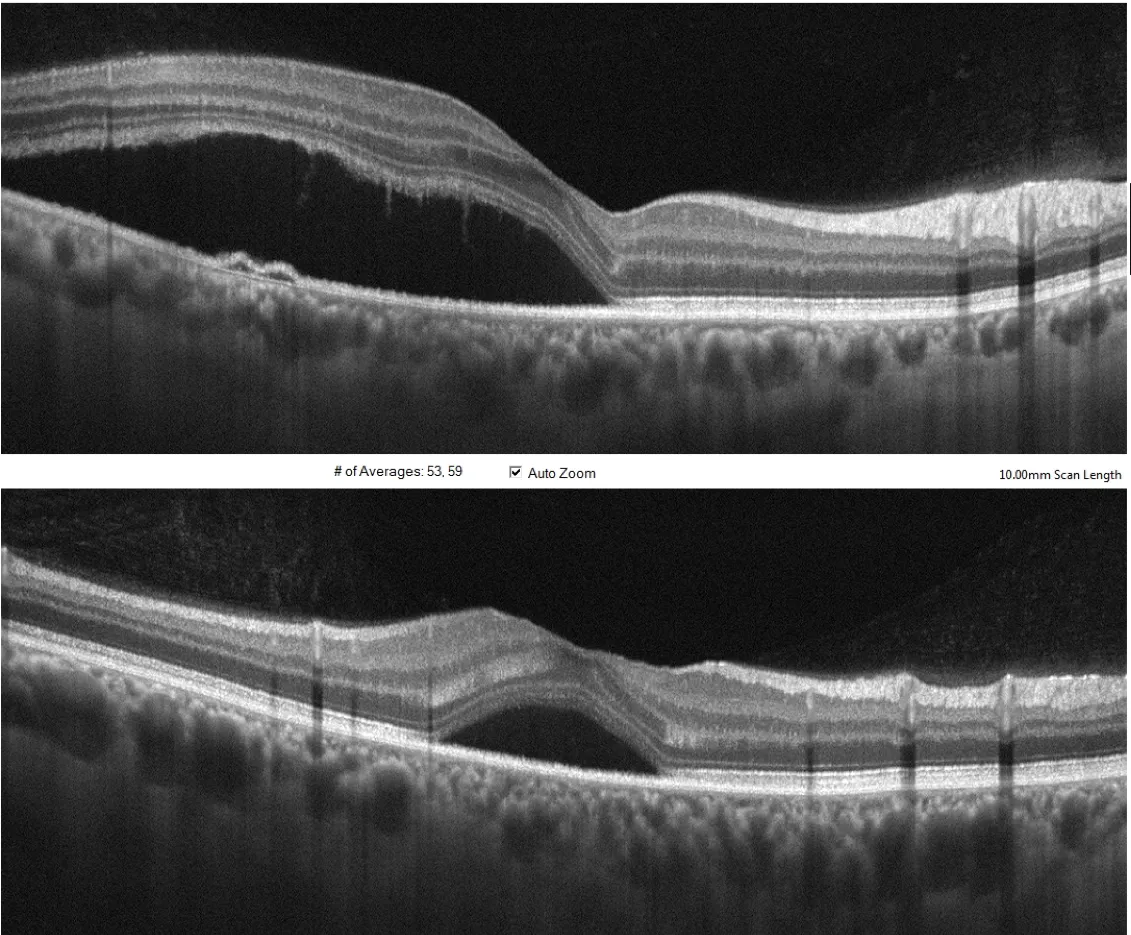

Différentes incidences de coupe 2D par imagerie OCT de la région maculaire d'un patient présentant une bulle de DSR(Décollement séreux rétinien)

Les décollements séreux de la CRSC, qu’il ne faut pas confondre avec les décollements de rétine reghmatogènes, sont dus à l’apparition de points de fuites qui seraient liés à une hyperperméabilité, un épaississement et à une modification structurelle du réseau vasculaire profond sous la rétine qu ‘on appelle la choroïde . Cette entité rentre dans le spectre de maladie dénommé « Pachychoroïde ».

Troncs choroïdien dilatés dans le cadre d'une Pachychoroïde

Le diagnostic initial est établi grâce à l’imagerie tomographique appelée OCT (tomographie en cohérence optique).

Cet examen met en évidence le soulèvement rétinien localisé ainsi que l’épaississement de la choroïde sous-jacente. L’OCT permet également de détecter d’autres pathologies secondaires à la CRSC comme les néovaisseaux occultes sur pachychoroïde ou la vasculopathie polypoïdale choroïdienne. La détection précoce de ces affections permet souvent d’éviter des complications sévères avec parfois des pertes irréversibles de l’acuité visuelle.